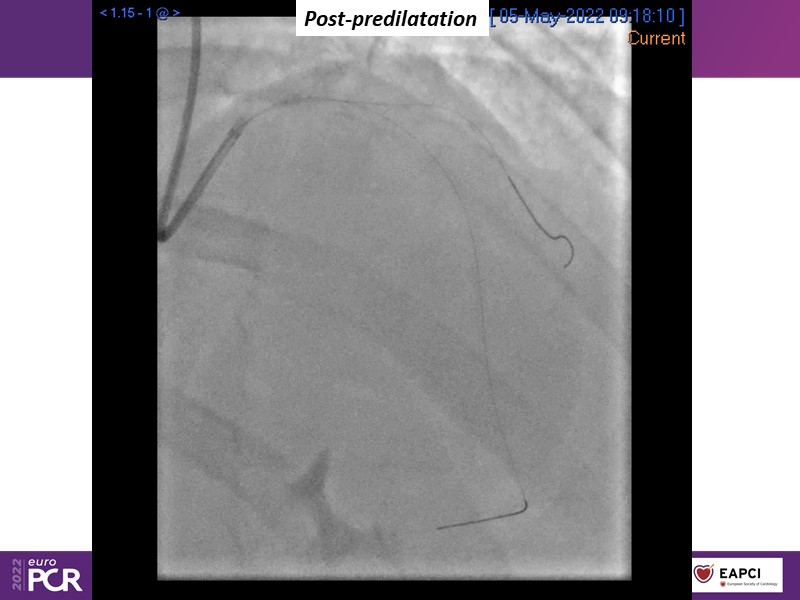

Alexandre Abizaid, Marco Valgimigli, Fazila Malik, Luca Testa, Patrick W. Serruys, Damiano Regazzoli, Kumar Prathap, and Sandeep Basavarajaiah take turns in this session to discuss two innovative technologies: a stent platform with nanotechnology and a novel drug-coated balloon (DCB). These novel technologies both have unique features that could change daily practice and improve outcomes.

- To find out more about the application and mechanism of a sirolimus coated balloon for coronary artery disease treatment with case presentations in complex settings

- To understand how useful is a DES and DCB stent platform in complex coronary artery disease settings with case demonstrations and follow-up in diabetes mellitus